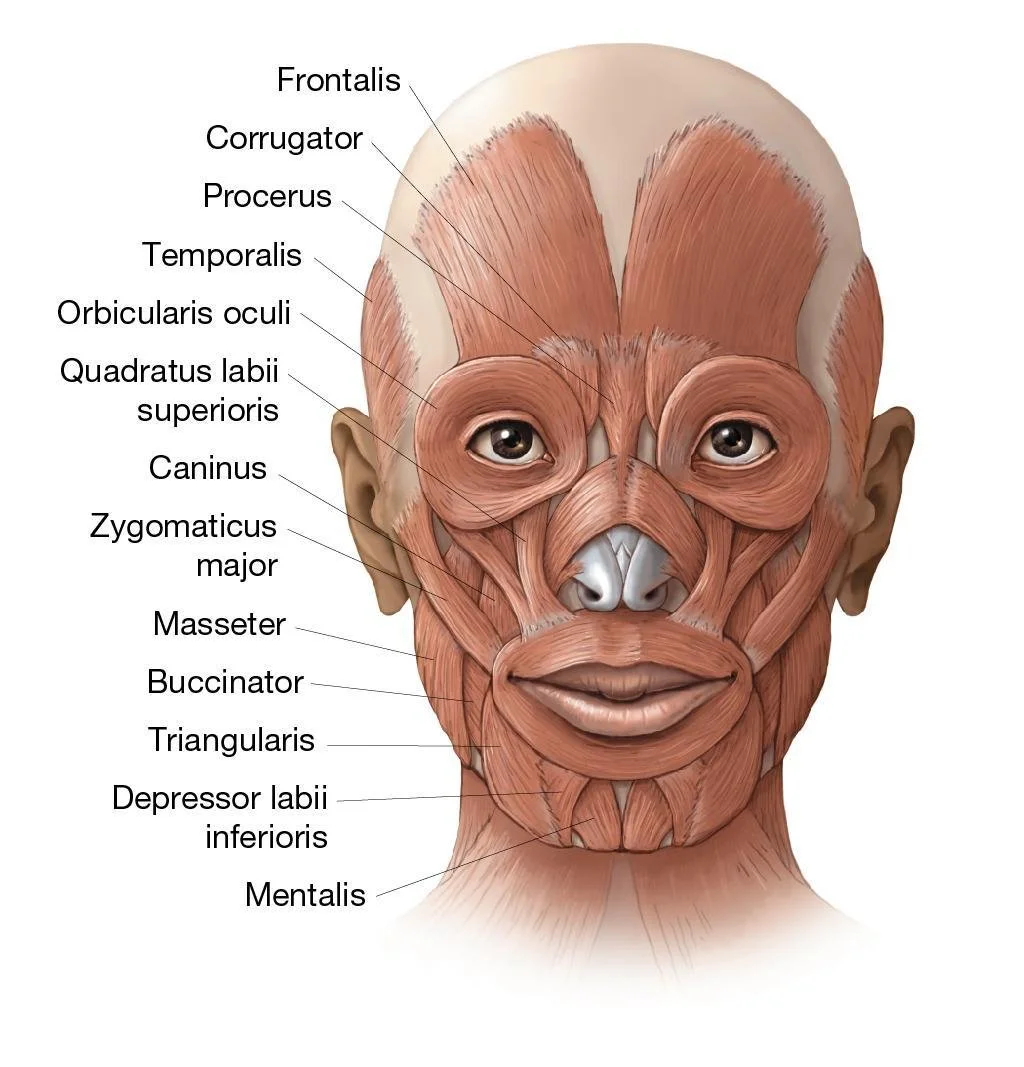

Medical Illustration

All images are works made for hire and are the exclusive property of the client. These are shown as sample purposes of my work only. For licensable work, please see my Illustration Services page.

Contract freelancer for many others, some examples of my work below.